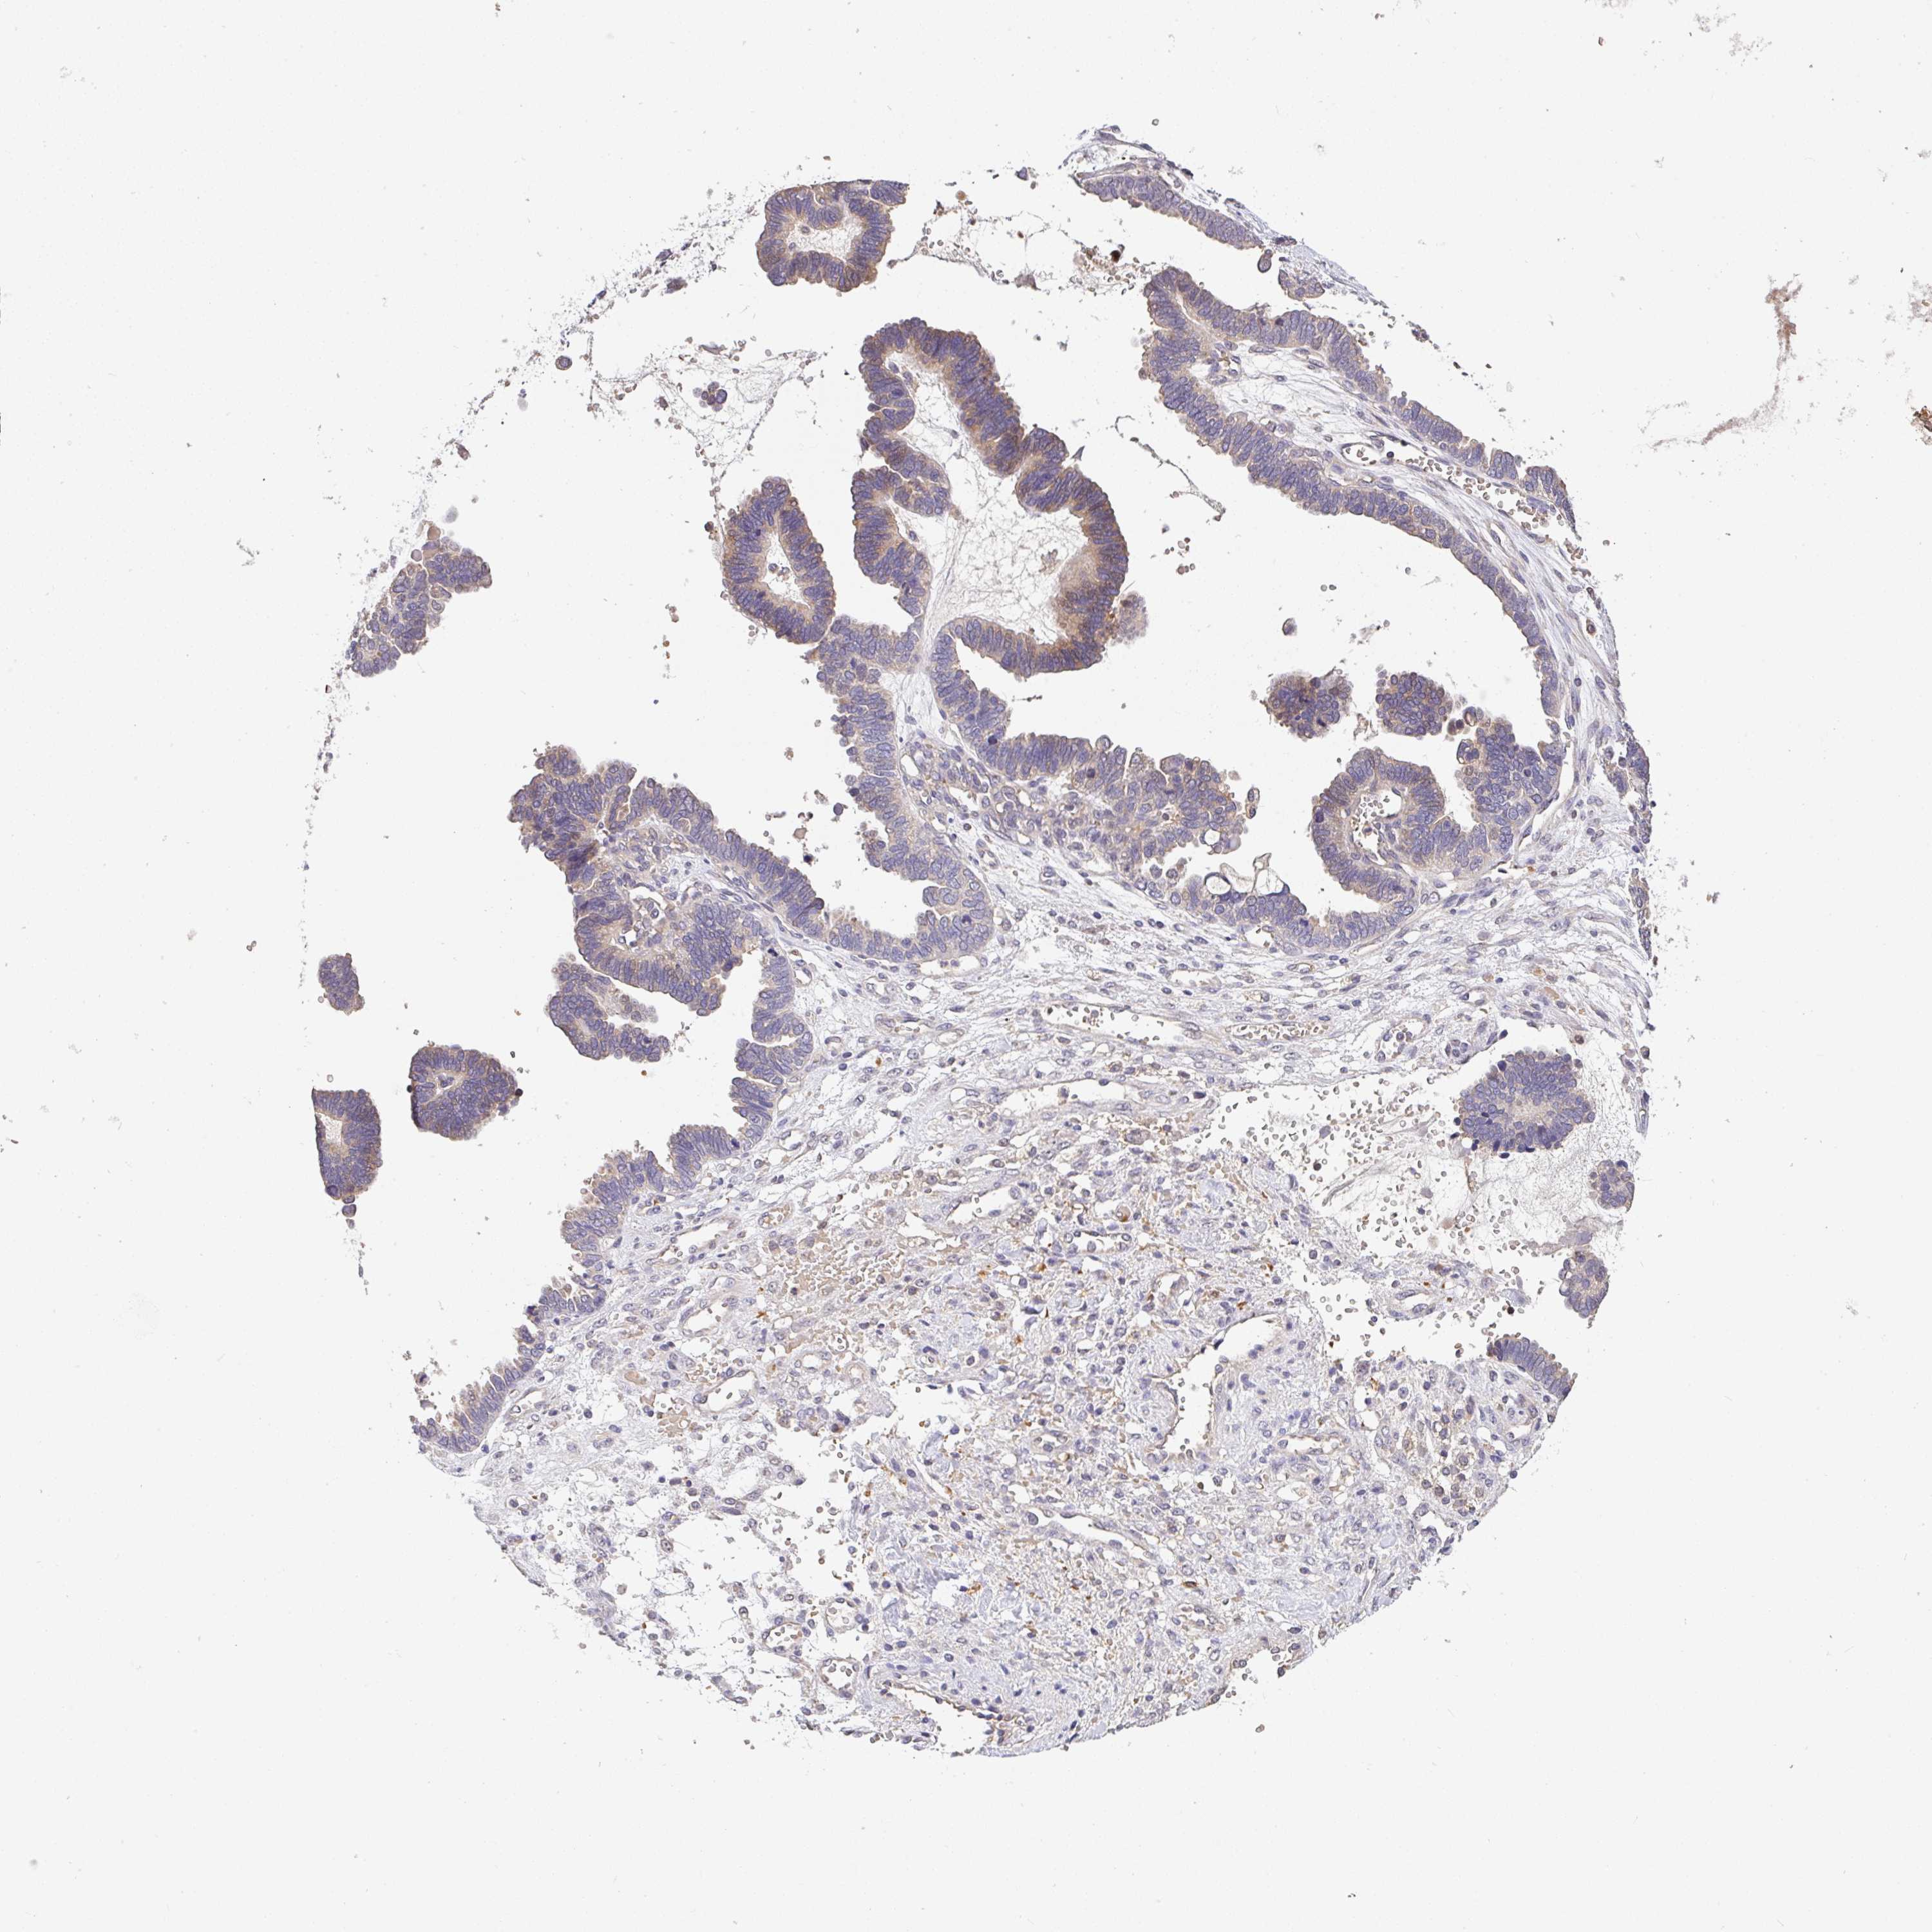

OVARIAN CANCER - Protein expressioni

A mouse-over function shows sample information and annotation data. Click on an image to view it in a full screen mode. Samples can be filtered based on level of antibody staining by selecting one or several of the following categories: high, medium, low and not detected. The assay and annotation is described here.

Note that samples used for immunohistochemistry by the Human Protein Atlas do not correspond to samples in the TCGA dataset.

Antibody stainingi

Antibody staining in the annotated cell types in the current human tissue is reported as not detected, low, medium, or high, based on conventional immunohistochemistry profiling in selected tissues. This score is based on the combination of the staining intensity and fraction of stained cells.

Each image is clickable and will lead to virtual microscopy that enables deeper exploration of all samples and also displays staining intensity scores, fraction scores and subcellular localization as well as patient and tissue information for each sample.

Antibody HPA056632

Cystadenocarcinoma, serous, NOS

Cystadenocarcinoma, mucinous, NOS

Carcinoma, endometroid